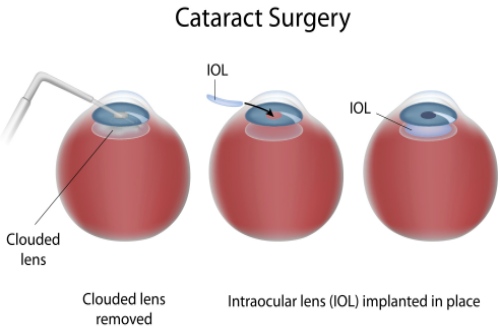

白内障手术是一种非常常见且安心的眼科手术,通常采用超声乳化技术将模糊的晶状体取出,然后植入人工晶状体以改善眼部视力。